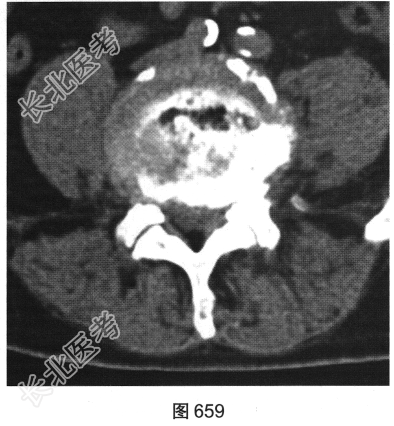

- 多项选择题2.[提示]患者行腰椎X线及CT检查,见图655~图659。患者有哪些阳性影像学表现( )

A、椎间盘“真空现象”

B、腰椎前滑脱

C、椎间盘膨出、突出

D、腰椎轻度侧弯

E、椎小关节骨质增生硬化

F、腰椎间隙变窄